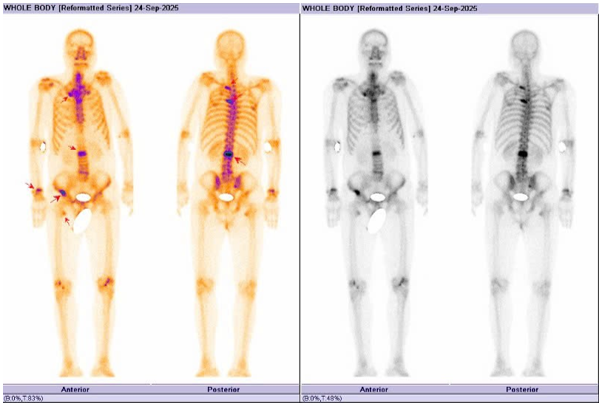

Sau đó, bệnh nhân được chụp PET/CT toàn thân, một phương pháp y học hạt nhân hiện đại, rất có giá trị trong phát hiện các tổn thương, đặc biệt là các tổn thương di căn hạch và di căn xa. Phim chụp cho thấy bệnh nhân có rất nhiều tổn thương tại nhu mô phổi hai bên, tại tuyến thượng thận trái, tại xương nhiều vị trí và tại tuyến tiền liệt, tăng hấp thu FDG thể hiện tính chất ác tính (Hình 5).

Hình 5: Hình ảnh PET/CT cho thấy: 02 khối u phổi phải, kích thước lớn nhất 16 x 23 mm, xâm lấn vào trung thất (SUVmax: 17,8) và các nốt đặc nhỏ rải rác nhu mô hai phổi, tăng hấp thu FDG (SUV: 10,5) (mũi tên đỏ). Hình ảnh các tổn thương tại xương (mũi tên trắng) tương ứng với các vị trí tổn thương quan sát thấy trên xạ hình xương (SUVmax: 22,2). Hình ảnh nốt tuyến thượng thận trái(mũi tên xanh), tăng hấp thu FDG (SUVmax: 15,2). Hình ảnh tăng hấp thu FDG tại vùng chuyển tiếp,vùng ngoại vi bên phải tuyến tiền liệt và thành dưới bàng quang (SUVmax: 17,1) (mũi tên vàng).